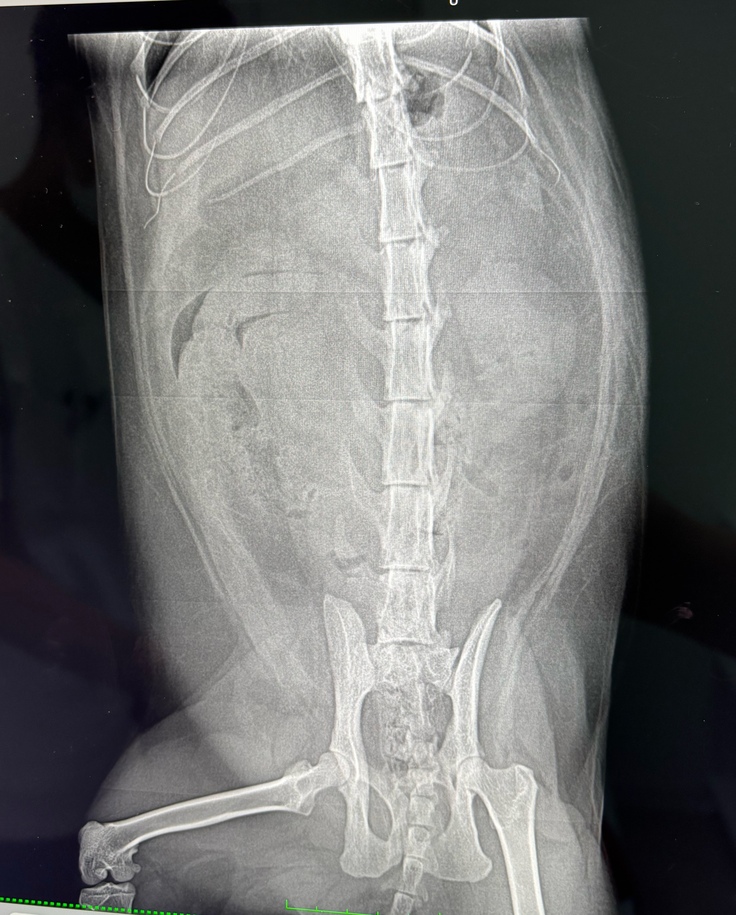

腹水がたまってきたため、緊急手術で腸に絡まっていた糸と毛玉を取り除きました。

当時のレントゲン

このときは「これで大丈夫」と思っていました。